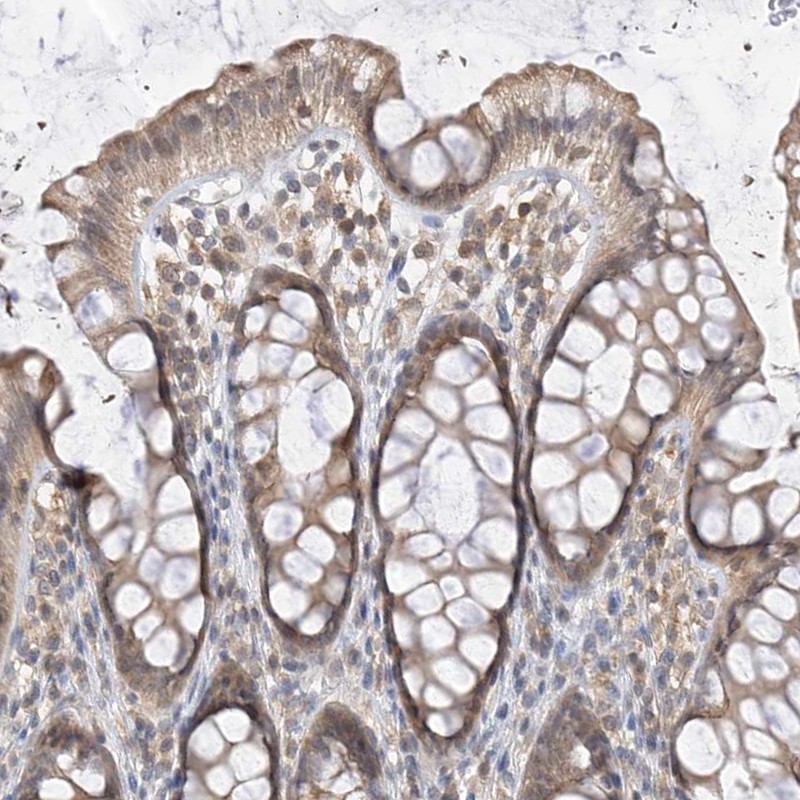

Immunohistochemical staining of human rectum shows moderate cytoplasmic positivity in glandular cells.